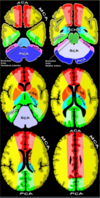

Irrigação do parênquima encefálico - diagrama

Escore para avaliar a extensão de um AVC de cerebral média na TOMOGRAFIA. Consiste em uma pontuação total de 10 pontos para as áreas irrigadas pela ACM: - No nível dos núcleos da base: Caudado, Lentiforme, Capsula interna e Insula; Região cortical anterior, média e posterior da ACM neste plano. - No nível acima dos núcleos da base (coroa radiata e centro semi-oval): Região cortical anterior, média e posterior da ACM neste plano.

ASPECTS normal recebe pontuação de:

10 Para cada área acometida é retirado 1 ponto do escore ASPECTS